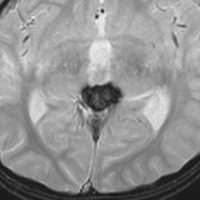

松果体芽腫グレード4の症例

水頭症で発症した6歳児で,4cmくらいある大きな松果体芽腫でした。大学病院で第3脳室開窓術と生検術をして,脳脊髄照射30グレイ(20分割),局所60グレイ(35分割)の放射線治療が行われました。さらにシスプラチンを基剤とした化学療法が3コース行われましたが,放射線で縮小した腫瘍は少し増大してしまいました。

放射線化学療法後の画像です。腫瘍境界は不明瞭(左)で,腫瘍内出血(中央)して,左の視床に浸潤しています。かなりリスクは高いのですが,これを開頭手術で全摘出しました(右),この時点で完全寛解 CR です。この後にさらに化学療法と幹細胞移植(PBSCT,大量化学療法)が加えられました。